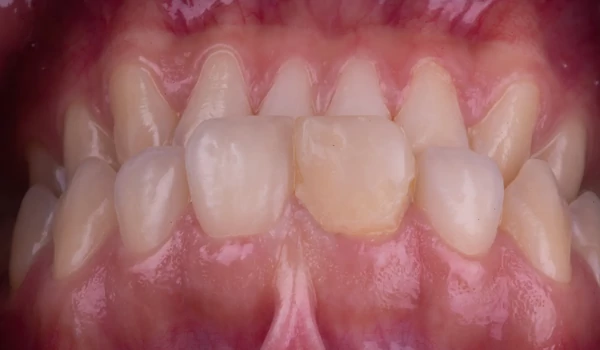

2. Core build-upÜvegszál erősítésű kompozit alapot alkalmaztak a fog szerkezetének stabilitásához. A bonding felületet foszforsavval maratták, majd CLEARFIL™ Universal Bond Quick univerzális ragasztót kentek fel. A core-t CLEARFIL MAJESTY™ ES-2 Premium A1D kompozittal építették fel kuraraynoritake.eu. |